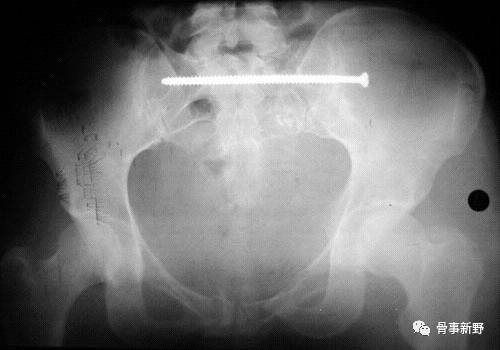

(5)置入合适长度的 7.3mm空心拉力螺,再次多角度透视确认螺钉位置。

(4)骶髂螺钉必须沿着S1椎弓根块进入椎体,保持全程在骨内。第一枚螺钉在上方,正位透视位于椎体中部靠近上终板,第二枚螺钉位于椎体前半部的下方。( 参考文献:Marvin Tile主编,邱贵兴主译,骨盆与髋臼骨折,2006)

通过置入第二枚螺钉,或与其它固定方式组合,构成三角固定,可明显增加后环稳定性。